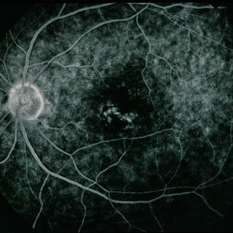

BRVO - Massive Exudate from Collaterals

Feb 24 2014 by David Callanan, MD

66-year-old female with BRVO - massive exudate from collaterals, 20/70 OD; 20/25 OS in 1985; +HTN, glaucoma; 20/200 OD 1987.

Condition/keywords: branch retinal vein occlusion (BRVO), collaterals, exudate